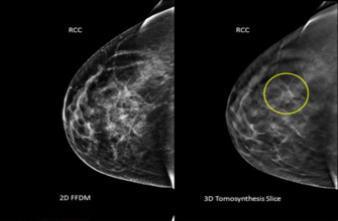

La mammographie en 3D combine deux techniques : la mammographie digitale traditionnelle et la tomosynthèse qui produit une série de tranches d’1 mm d’épaisseur. Cela permet d’obtenir une image beaucoup plus précise du sein. Pour les patientes, rien ne change : elles se positionnent de la même manière sur l’appareil, et l’examen ne demande que quelques secondes de plus. Pour les médecins en revanche, la mammographie 3D est radicalement différente.

Les clichés plus clairs et plus précis obtenus par la 3D permettent de mieux identifier les différentes structures du sein. En passant en revue les résultats d’un demi-million d’examens pratiqués sur 13 sites différents, l’étude chiffre précisément les avantages de la mammographie en 3 dimensions. Le nombre de cancers du sein détectés grimpe de 29 %, et plafonne même à +41 % pour les seuls cancers invasifs. Les rappels à l’examen qui aboutissent sur une fausse alerte, eux, reculent de 15 %.